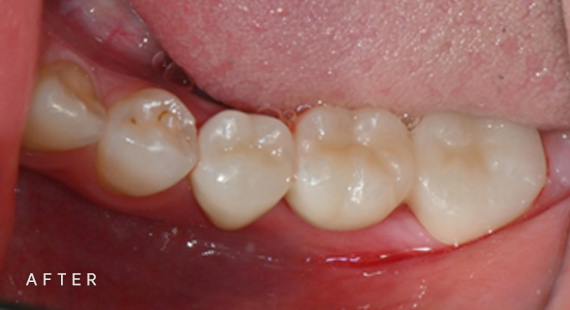

충치치료